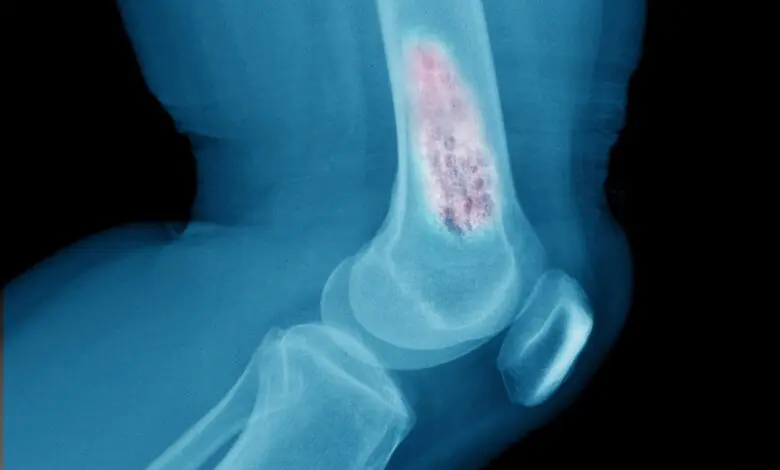

- Görüntüleme testleri: Doktorunuz, kemik tümörlerini görüntülemek ve tanımlamak için röntgen, bilgisayarlı tomografi (BT), manyetik rezonans görüntüleme (MRG), pozitron emisyon tomografisi (PET) veya kemik sintigrafisi gibi testler isteyebilir. Bu testler, tümörün tipini, evresini, konumunu ve yayılımını belirlemeye yardımcı olabilir.